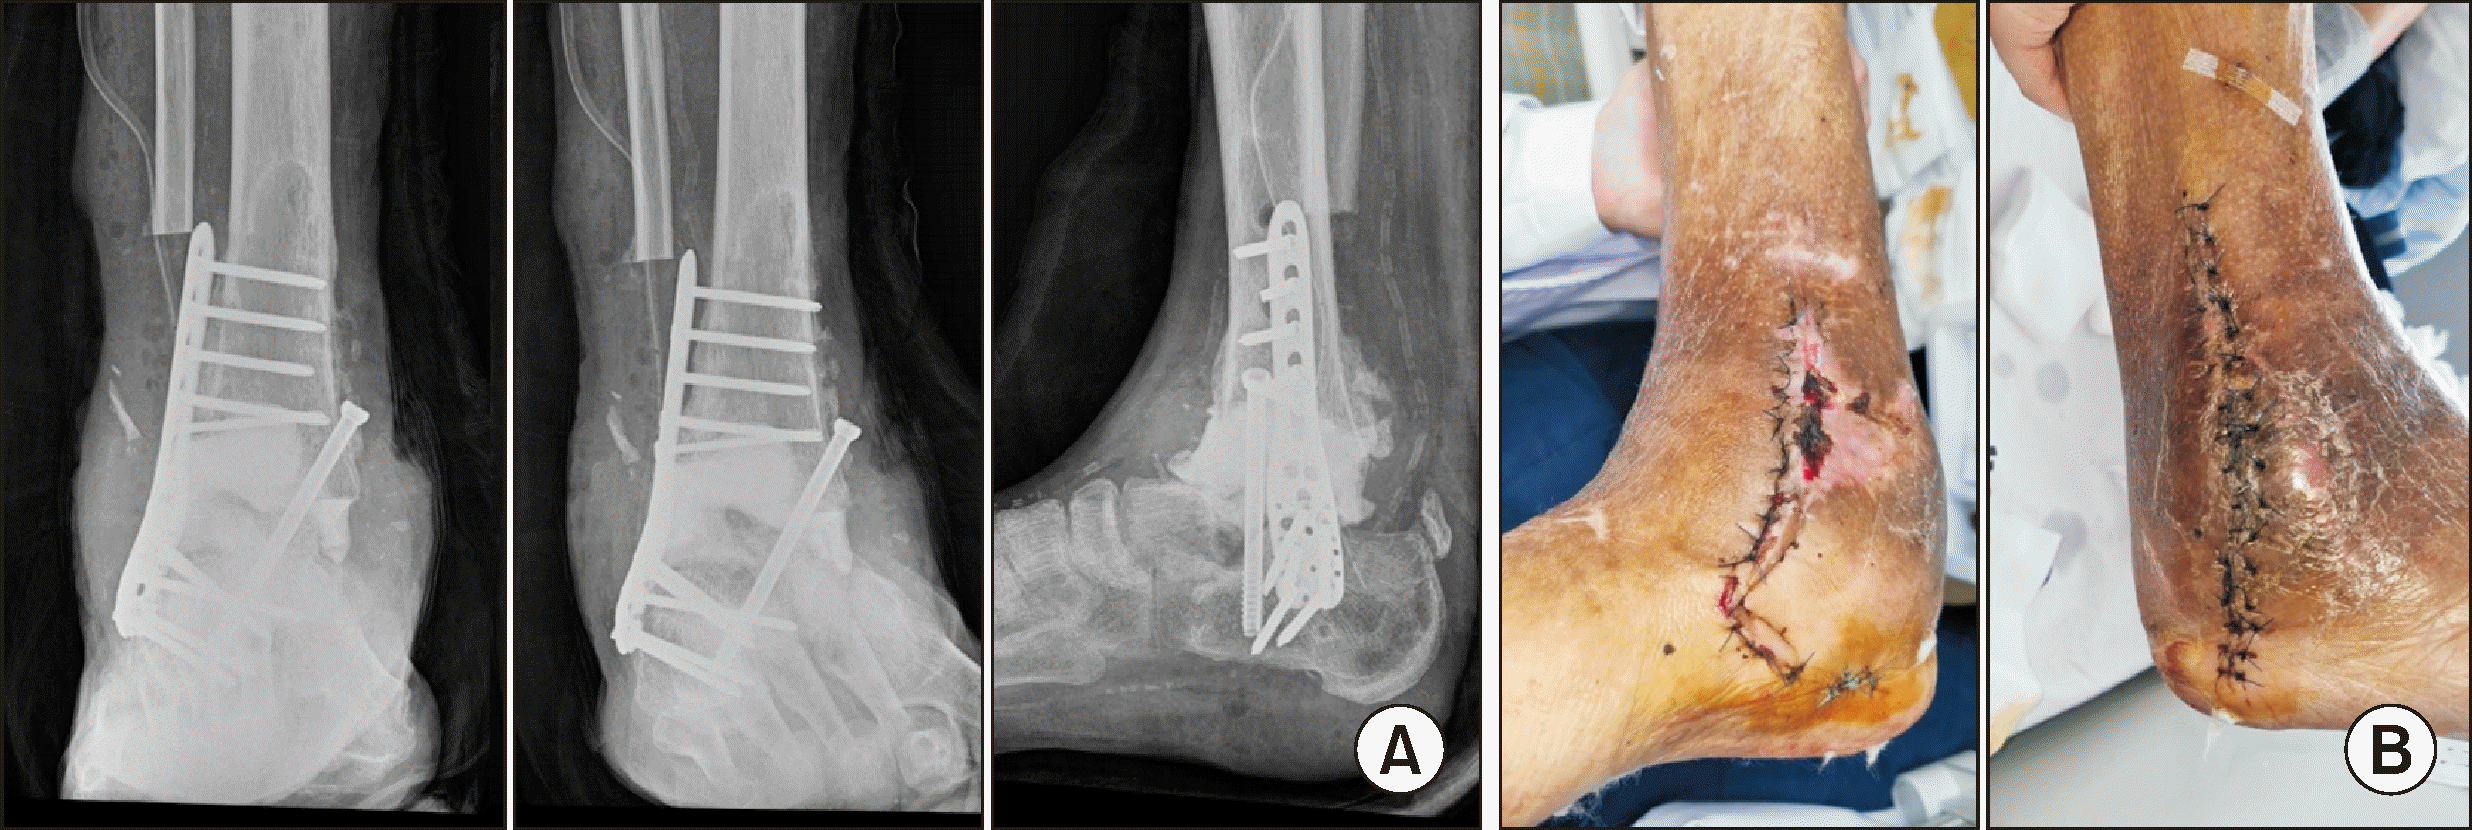

One week after applying the external fixator, tibiotalocalcaneal (TTC) fusion was performed using a retrograde T2 nail (T2 Alpha Retrograde Femur Nailing System, Stryker Corporation), and a fibular bone ostectomy was conducted to provide a bone graft at the fusion site (Fig. 7A). Additionally, there was a medial wound defect at the time of surgery, indicating the need for further interventions such as a flap in the future (Fig. 7B). Approximately 3 weeks after the TTC fusion, granulation tissue was observed in the medial wound. Kerecis GraftGuide (Kerecis Ltd.) was applied to cover the wound defect (Fig. 8).

Figure 7

(A) Post-operative radiograph after tibiotalocalcaneal fusion using a retrograde T2 nail. (B) Clinical findings showing a medial wound defect at the time of surgery.